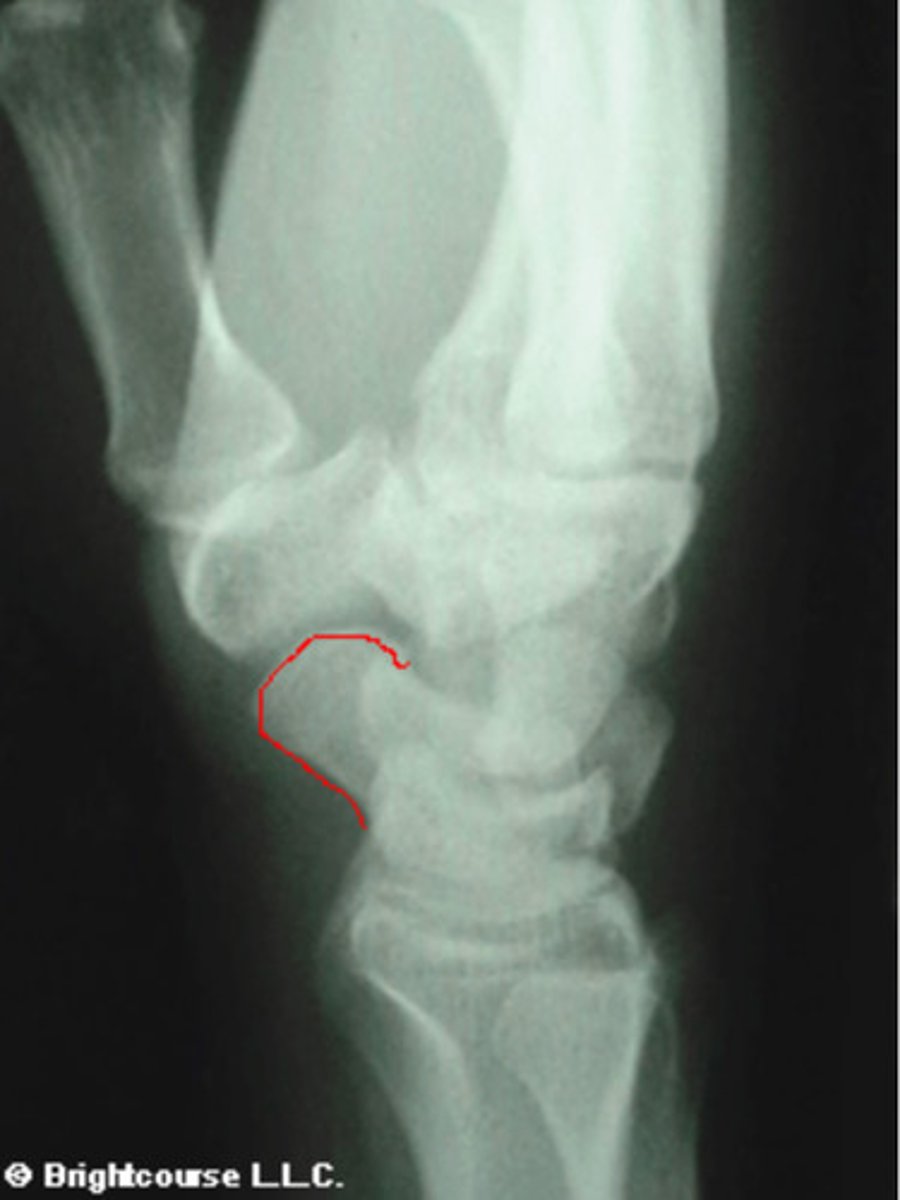

What structure is being circled in this image?

3 arcs of carpal alignment

What is being assessed in this image?

Scaphoid

What structure is being outlined in this image?